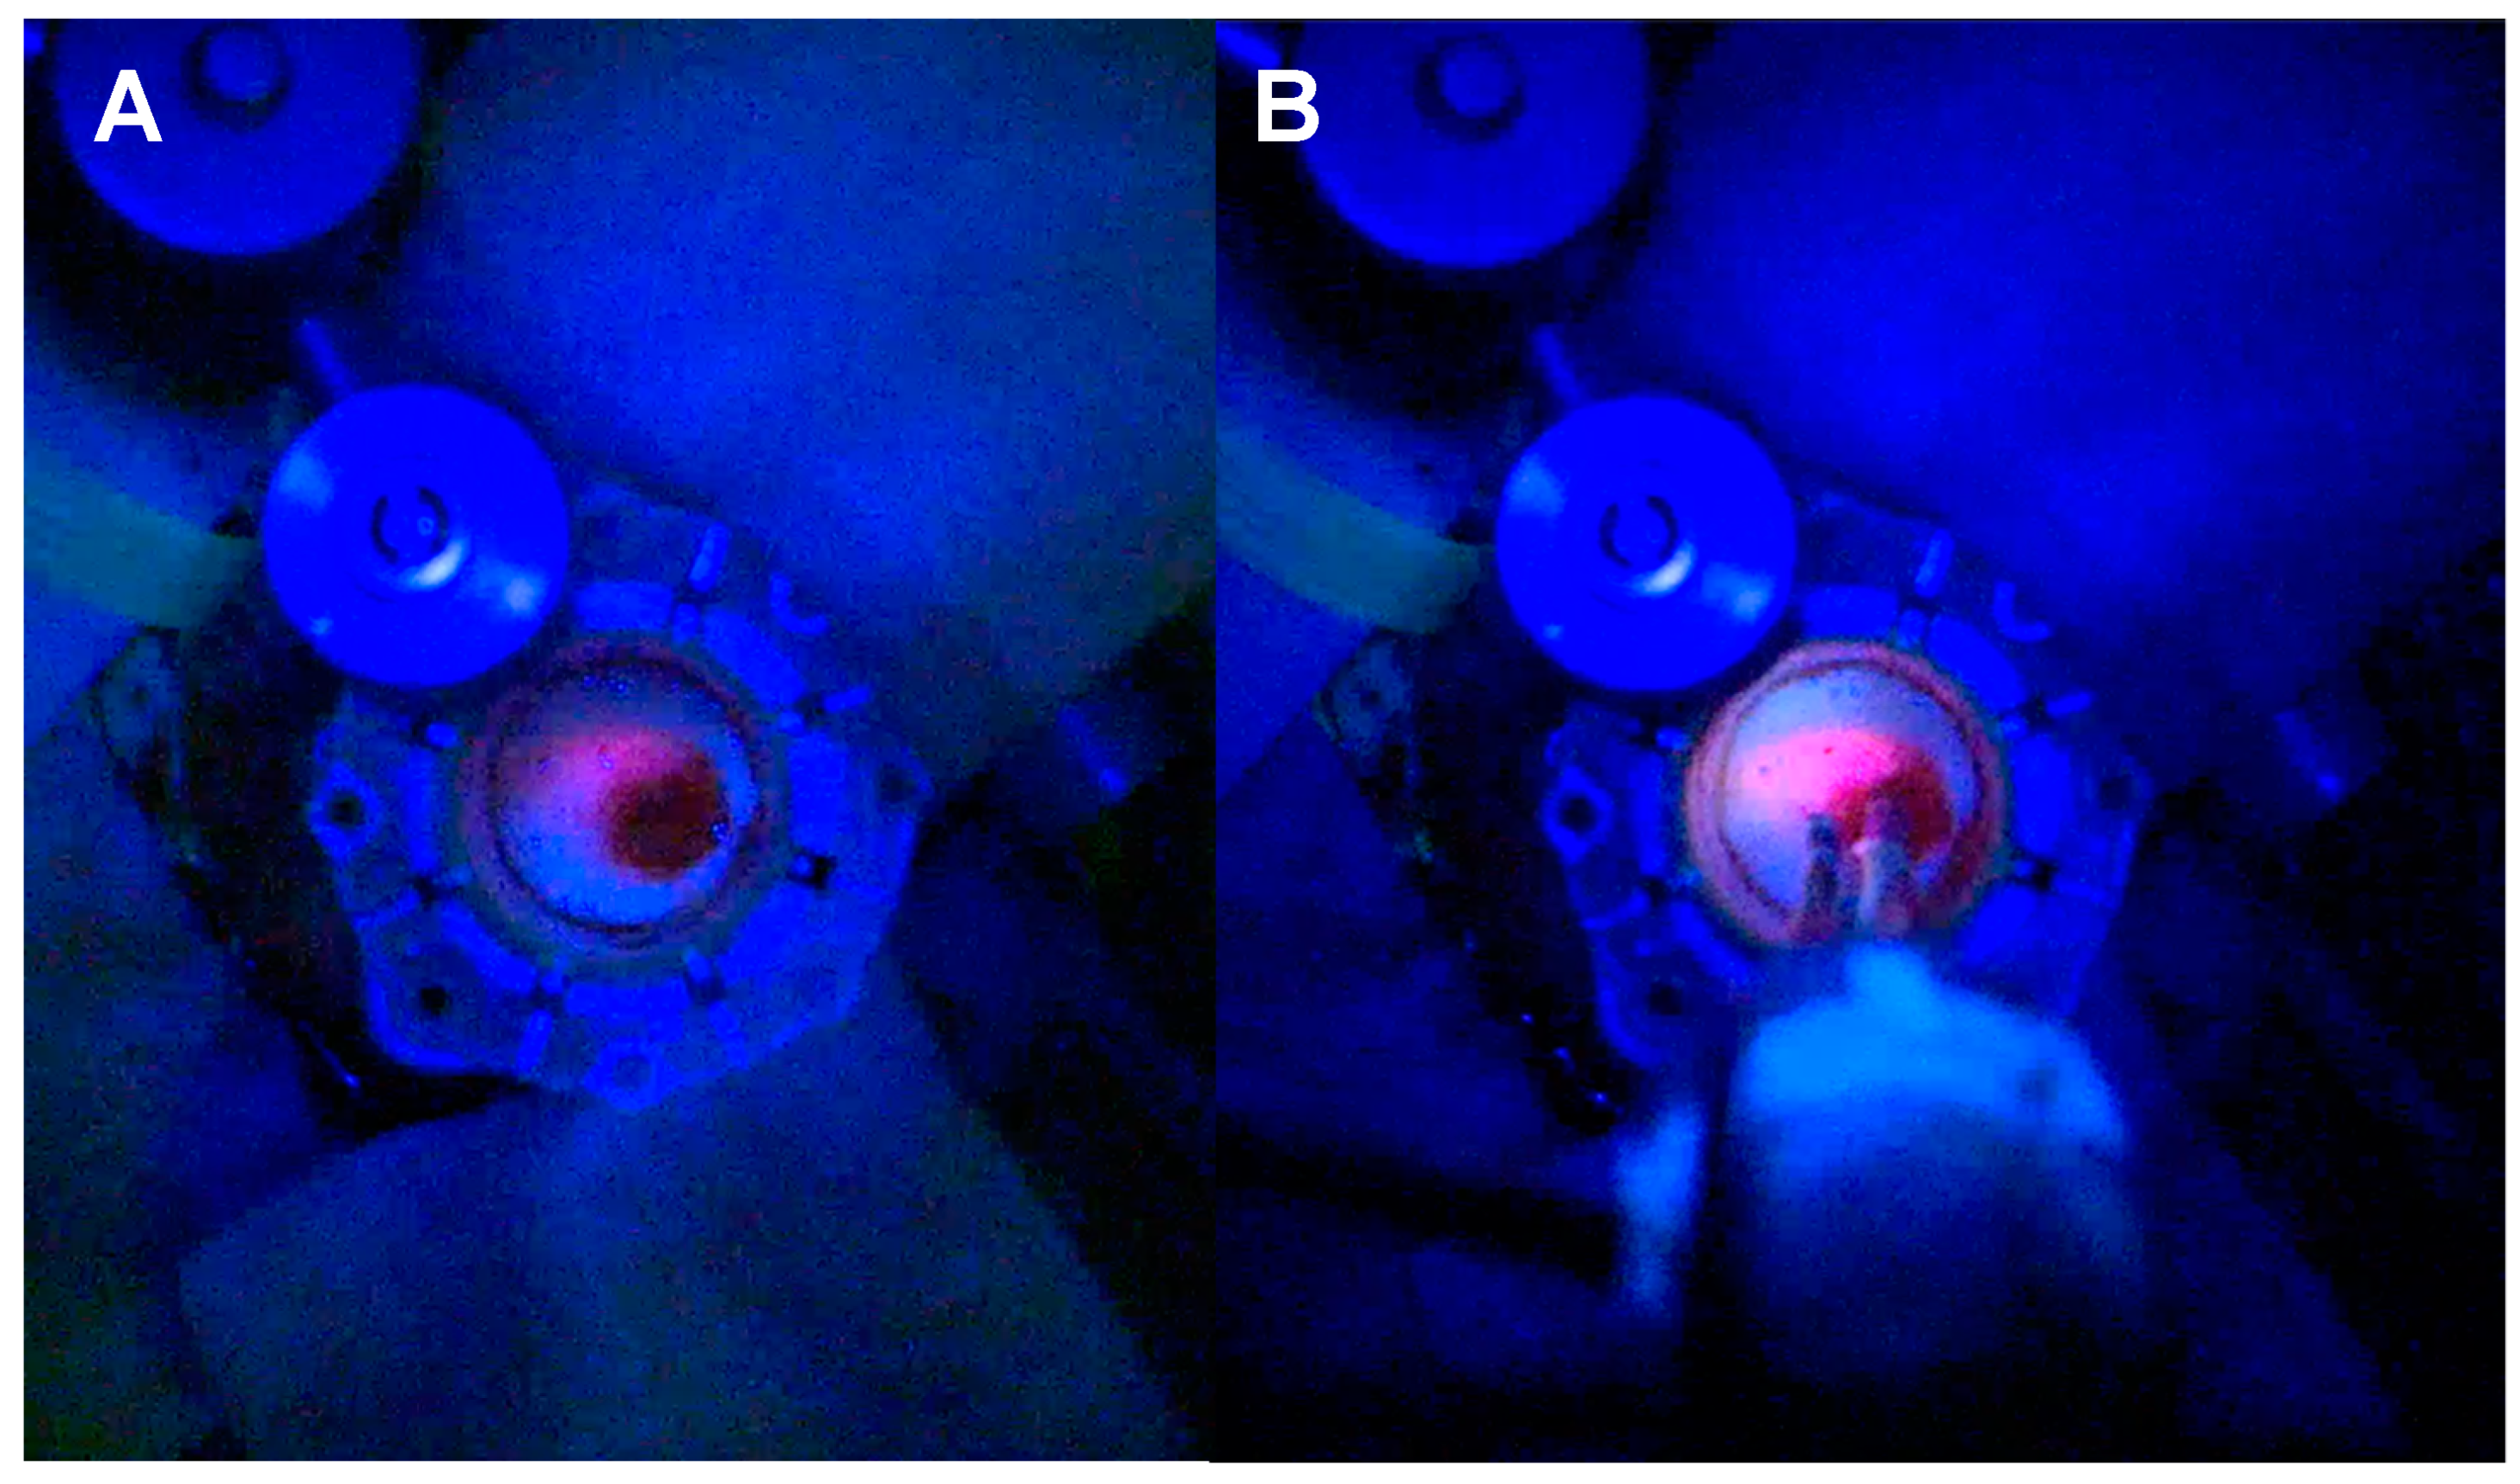

3.1.1. Tubular Retractor-Minimally Invasive Parafascicular Surgery (tr-MIPS)